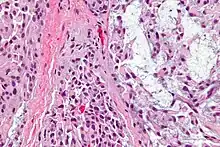

Myoepithelial cells (sometimes referred to as myoepithelium) are cells usually found in glandular epithelium as a thin layer above the basement membrane but generally beneath the luminal cells. These may be positive for alpha smooth muscle actin and can contract and expel the secretions of exocrine glands. They are found in the sweat glands, mammary glands, lacrimal glands, and salivary glands. Myoepithelial cells in these cases constitute the basal cell layer of an epithelium that harbors the epithelial progenitor. In the case of wound healing, myoepithelial cells reactively proliferate. Presence of myoepithelial cells in a hyperplastic tissue proves the benignity of the gland and, when absent, indicates cancer. Only rare cancers like adenoid cystic carcinomas contains myoepithelial cells as one of the malignant components.

Other Cancers Involving This Type of Cell

- Adenomyoepithelioma of the breast- A (usually) benign tumor of the breast composed of Myoepithelial and Adeno (glandular) cells.

- Myoepithelioma of the Breast- A usually benign or exceedingly rare malignant tumor of the breast which mimics IDC but with cells resembling adenoid cysts. If malignant, this is also known as a Myoepithelial Carcinoma.